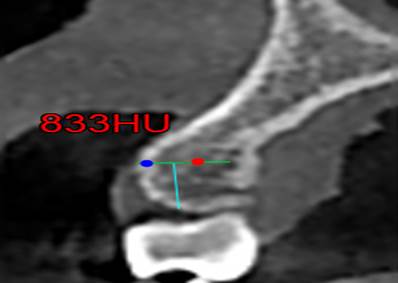

Los datos recopilados fueron número de registro, edad del paciente, sexo, corte de la zona maxilar interradicular de donde se tomó la muestra. Se llego a un consenso con los expertos donde se tomó en cuenta los siguientes puntos anatómicos para la toma de la medida mediante Unidades Homsfield.

§ Por cada corte se tomaba en cuenta 0.5 mm desde la cresta alveolar hacia la zona de la línea mucogingival. (imagen 1)

§ Con una profundidad de 0.6 mm a través de la cortical hacia la tabla ósea que es el valor mínimo de un microtornillo ortodóntico en sentido horizontal (imagen 2) interradicular. Las Zonas a medir fueron:

Finalmente se mide las Unidades Hounsfield (UH) a 6 mm intraóseo e interradicular. (Imagen 1,2,3,4).